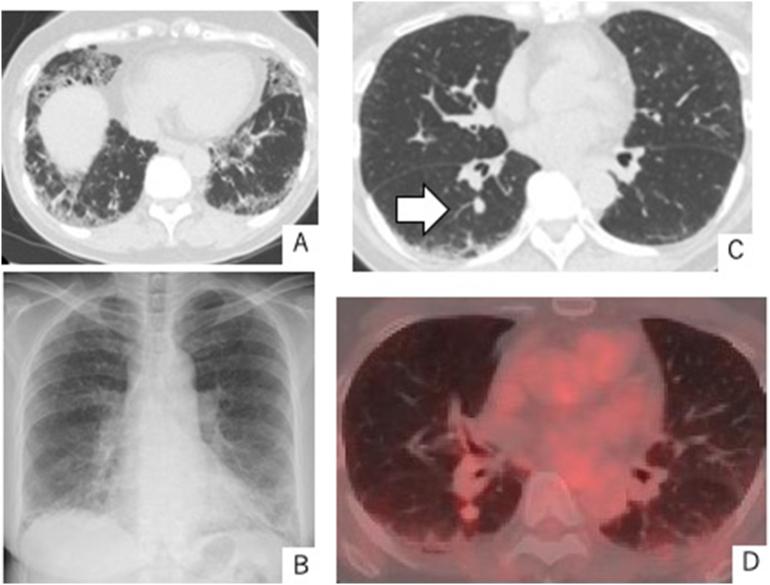

A 64-year-old woman who had never smoked presented with cough 2 years earlier. Chest CT showed that the nodule in the right lower lobe had slowly enlarged to 12 × 10 mm. We suspected primary lung cancer and performed video-assisted thoracoscopic right S6 segmentectomy. Histopathological evaluation of the resected specimen revealed crystal-storing histiocytosis. As of 6 months postoperatively, no recurrence has been identified.

一名64岁从不吸烟的女性于2年前出现咳嗽症状。胸部CT显示右下叶结节缓慢增大至12×10毫米。我们怀疑是原发性肺癌并进行了电视辅助胸腔镜右S6段切除术。对切除标本的组织病理学评估显示为晶体储存性组织细胞增多症。截至术后6个月,未发现复发。